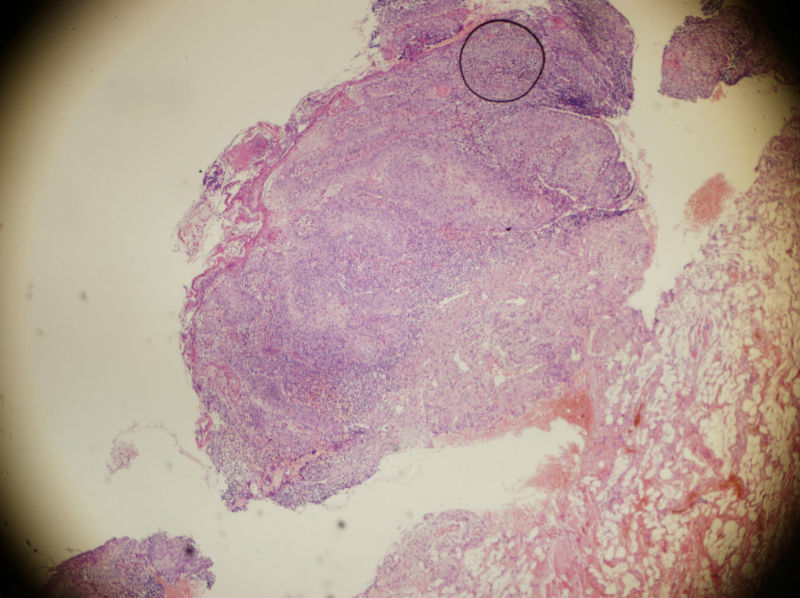

男,45岁,上唇菜花样肿物,请老师指教

图3